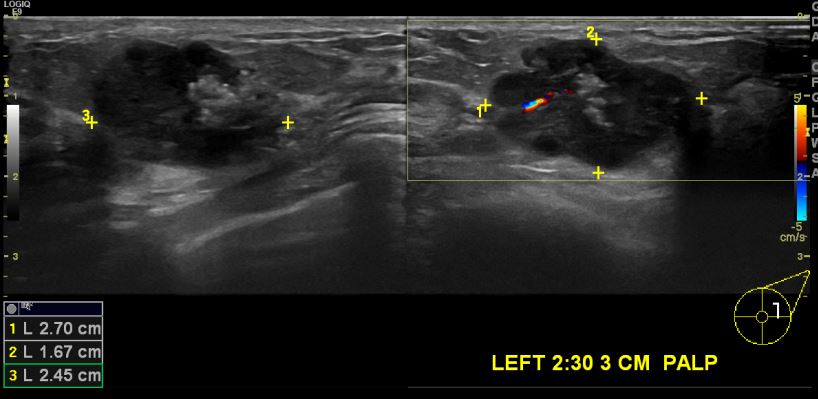

상기환자 좌측에 만져지는 멍우리로 내원하신 30대 여성분으로 좌측 2시 30분 방향에 3cm 떨어진 거리의 만져지는 혹 중심핵생검 시행하여 좌측 침윤성 유관암 진단되었습니다.